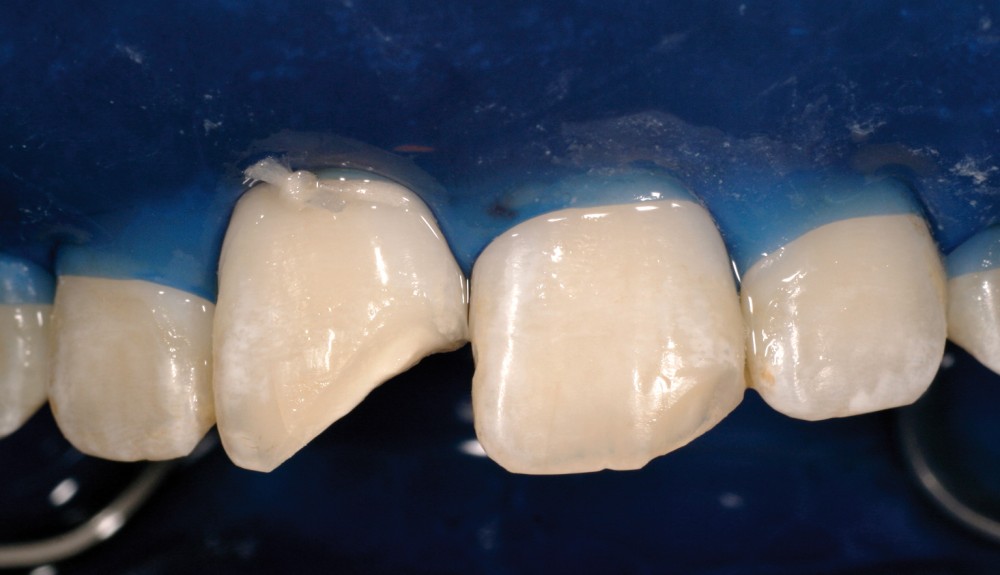

Restauration esthétique directe d’un angle incisif fracturé

Les restaurations antérieures en composite font partie de nos plans de traitement au quotidien. Cependant, leur apparente complexité et leur résultat souvent aléatoire laissent à penser que cette solution n’est seulement accessible qu’à « quelques artistes ». C’est pourquoi, le but de cet article est de proposer, au travers d’un cas clinique, une méthode fiable et reproductible en insistant sur les étapes cliniques essentielles à leur réussite.